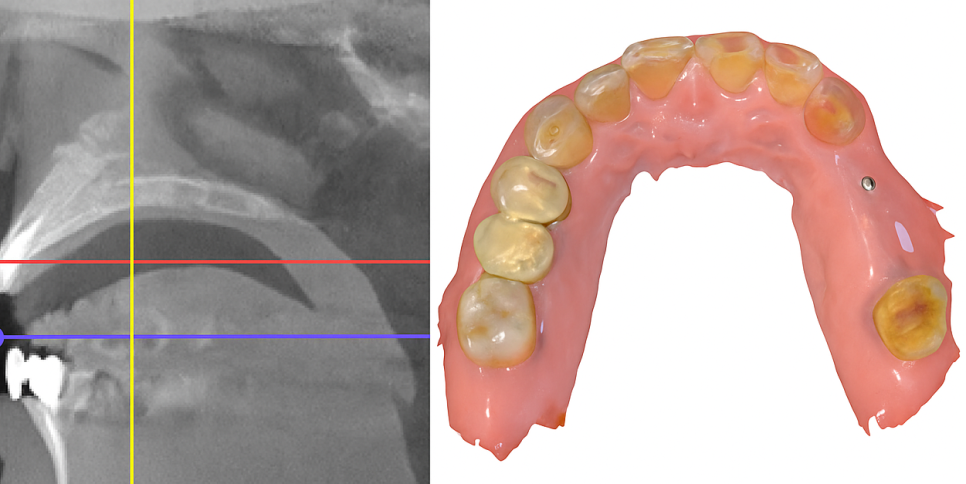

CT 촬영을 통해

턱뼈의 높이, 두께, 밀도를 정확히

평가해야 됩니다.

정확한 3D 진단 및 계획이 중요합니다.

수술 전에 3차원 CT와 구강 스캐너를

사용해 상악동의 해부학적 구조를

정밀 분석합니다.

잔존 뼈의 두께, 상악동 막의 위치와

두께, 임플란트 심을 위치를

면밀히 검토합니다.

네비게이션 시스템을 활용하면

픽스처 식립과 상악동 거상 위치를

미리 시뮬레이션할 수 있습니다.